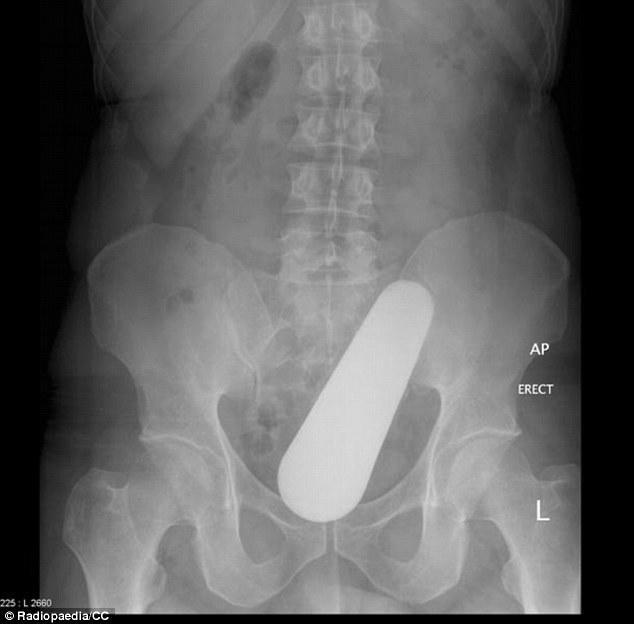

Pour prouver les difficultés du métier de radiologue aux étudiants, un centre de recherche a publié les clichés des cas les plus compliqués et insolites d'objets coincés dans le rectum de patients. Des images qui resteront dans les annales !

Comment ce pilon est-il arrivé là ? Selon le centre de recherche en radiothérapie Radiopaedia, il aurait pénétré dans le rectum d"un patient de 40 ans "tombé par terre en cuisinant".